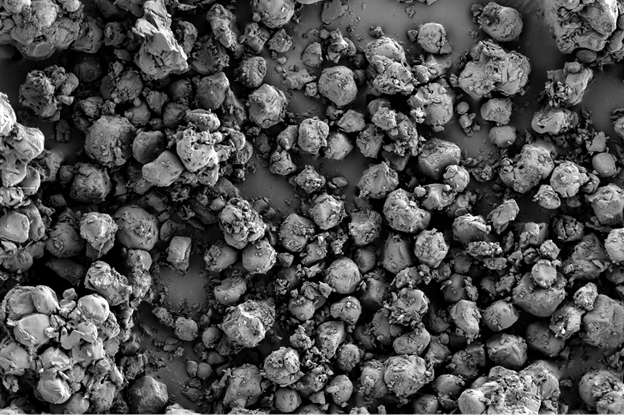

Так, при плановой проверке качества капсул с сульфатом глюкозамина с помощью оптического микроскопа были обнаружены мелкие дефекты на поверхности. Последующий анализ на СЭМ при высоком увеличении выявил микротрещины и прикрепленные пластинчатые частицы неправильной формы (рис. 1а). Морфология трещин указывала на их возможное происхождение в результате коррозии под напряжением, связанной с неравномерной сушкой покрытия и релаксацией полимерных напряжений. Инородные частицы по своей структуре (рис. 1b — чистая поверхность) отличались от матрицы капсулы.

Сопоставление с типичными микроорганизмами позволило исключить биологическую природу загрязнения; наиболее вероятным источником была признана неорганическая пыль из производственной среды или вспомогательных веществ. Эти данные послужили основой для корректировки режимов нанесения покрытия и ужесточения контроля чистоты в производственных помещениях.

Рис. 1а — Поверхность капсулы с сульфатом глюкозамина: визуализированы пластинчатые включения и микротрещины; загрязнения проникают в трещины. Изображения получены с помощью микроскопа LANSEM 30.